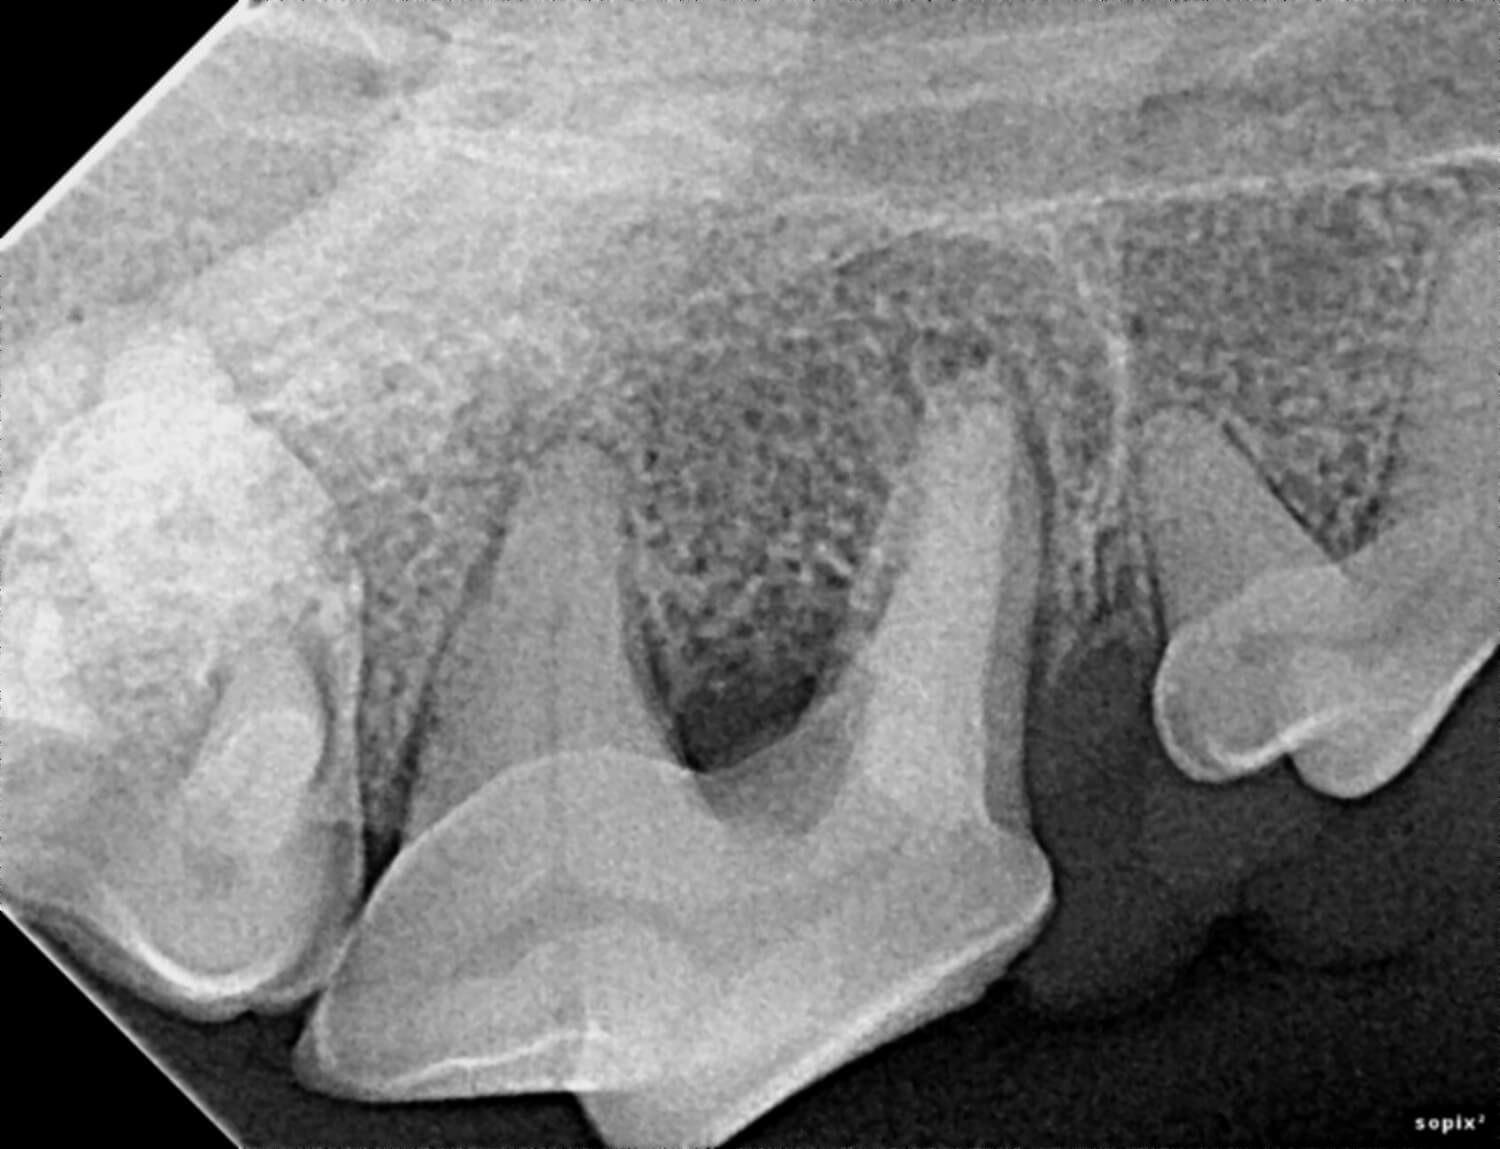

Our veterinarians use digital radiology to detect conditions such as tooth root abscesses, oral tumors, jaw fractures, and hidden dental disease. Early diagnosis enables timely treatment, reducing pain and preventing advanced dental complications.

Digital radiology plays a vital role in preventive health and advanced diagnosis for pets. Dental and oral conditions are often hidden below the gumline, where physical exams cannot detect them.

This imaging can reveal issues such as periodontal disease, infections, tooth resorption, and bone loss before they cause noticeable pain or lasting damage. Prompt diagnosis allows our team to provide targeted treatments that keep your pet comfortable and healthy.